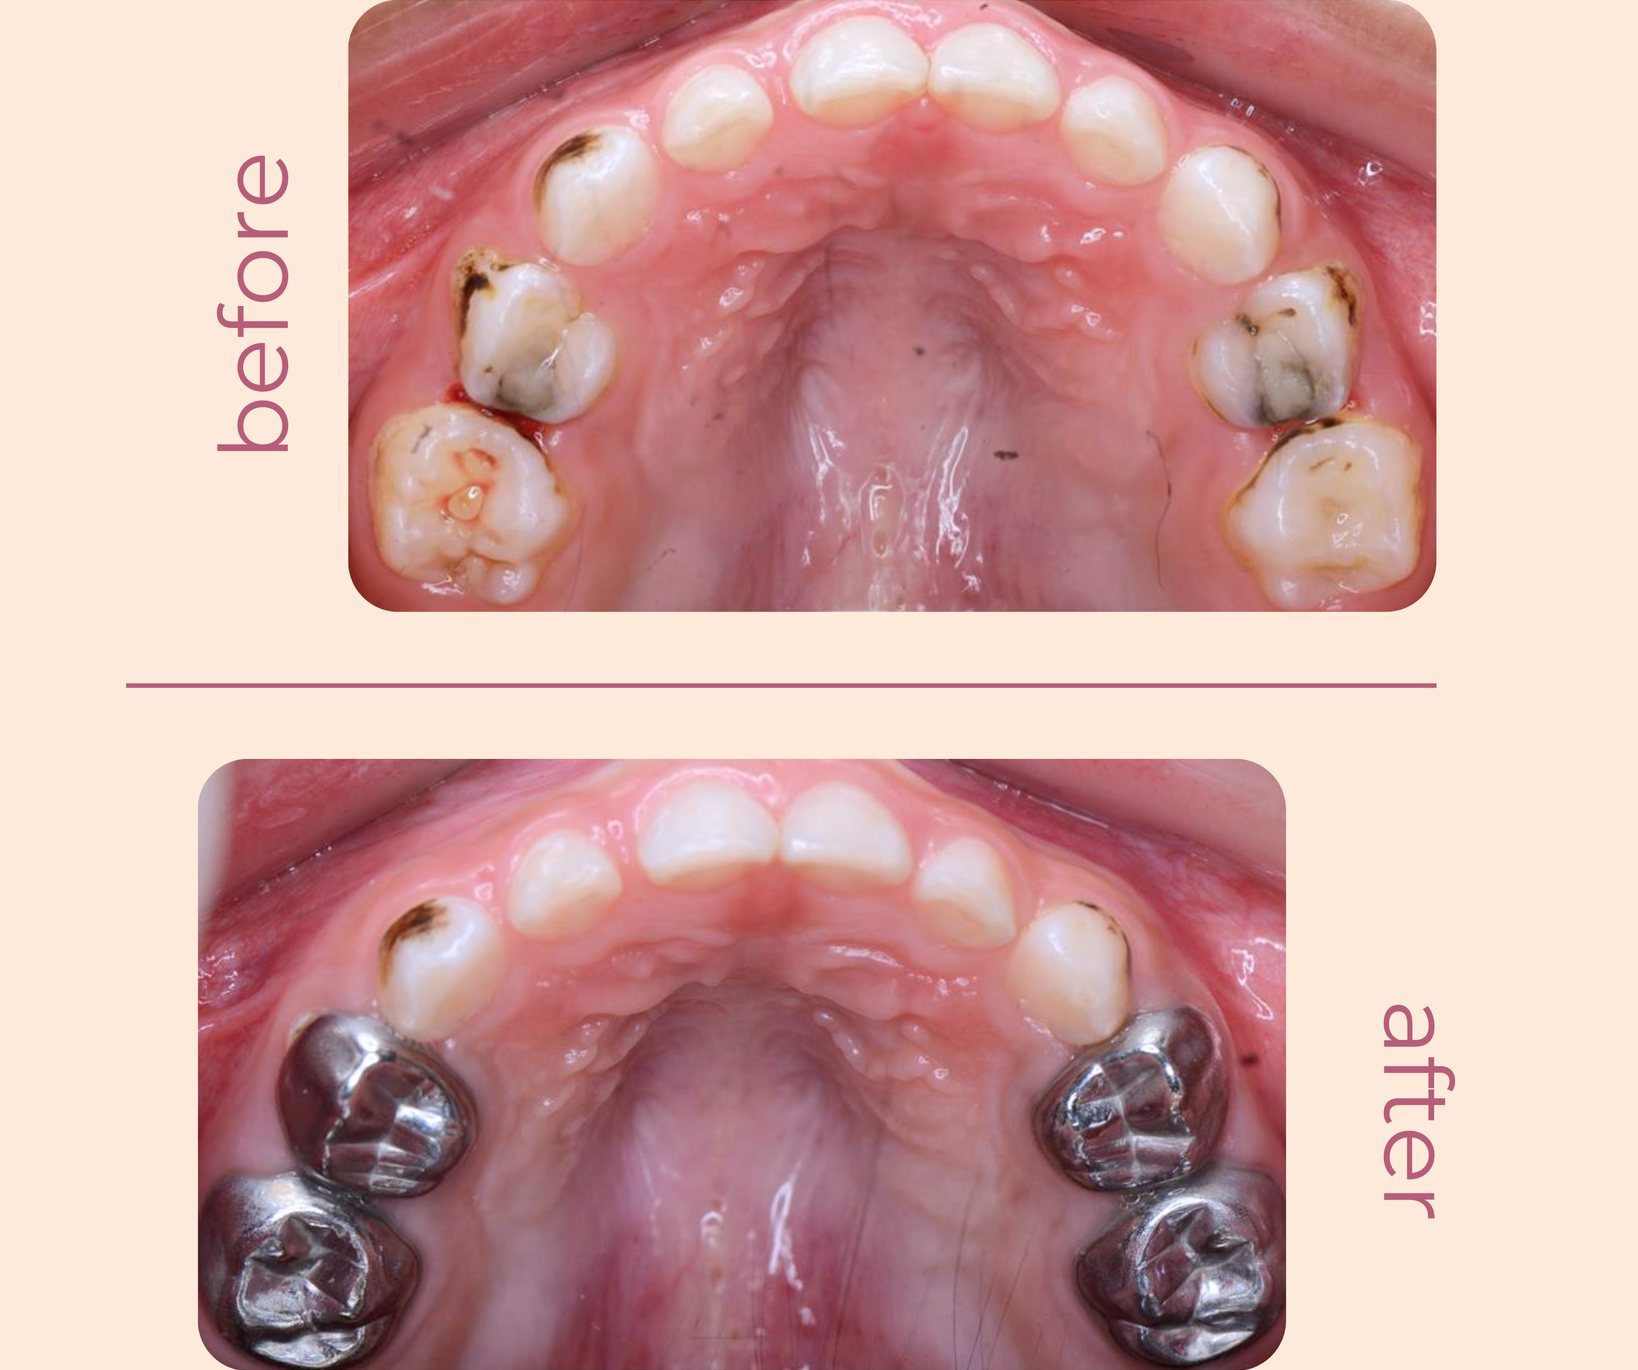

Hình Ảnh Trước & Sau Điều Trị

Minh chứng rõ ràng cho chất lượng và hiệu quả tại Nha khoa Như Ngọc – nơi mỗi khách hàng đều tìm lại được nụ cười tự tin sau quá trình điều trị và thẩm mỹ răng